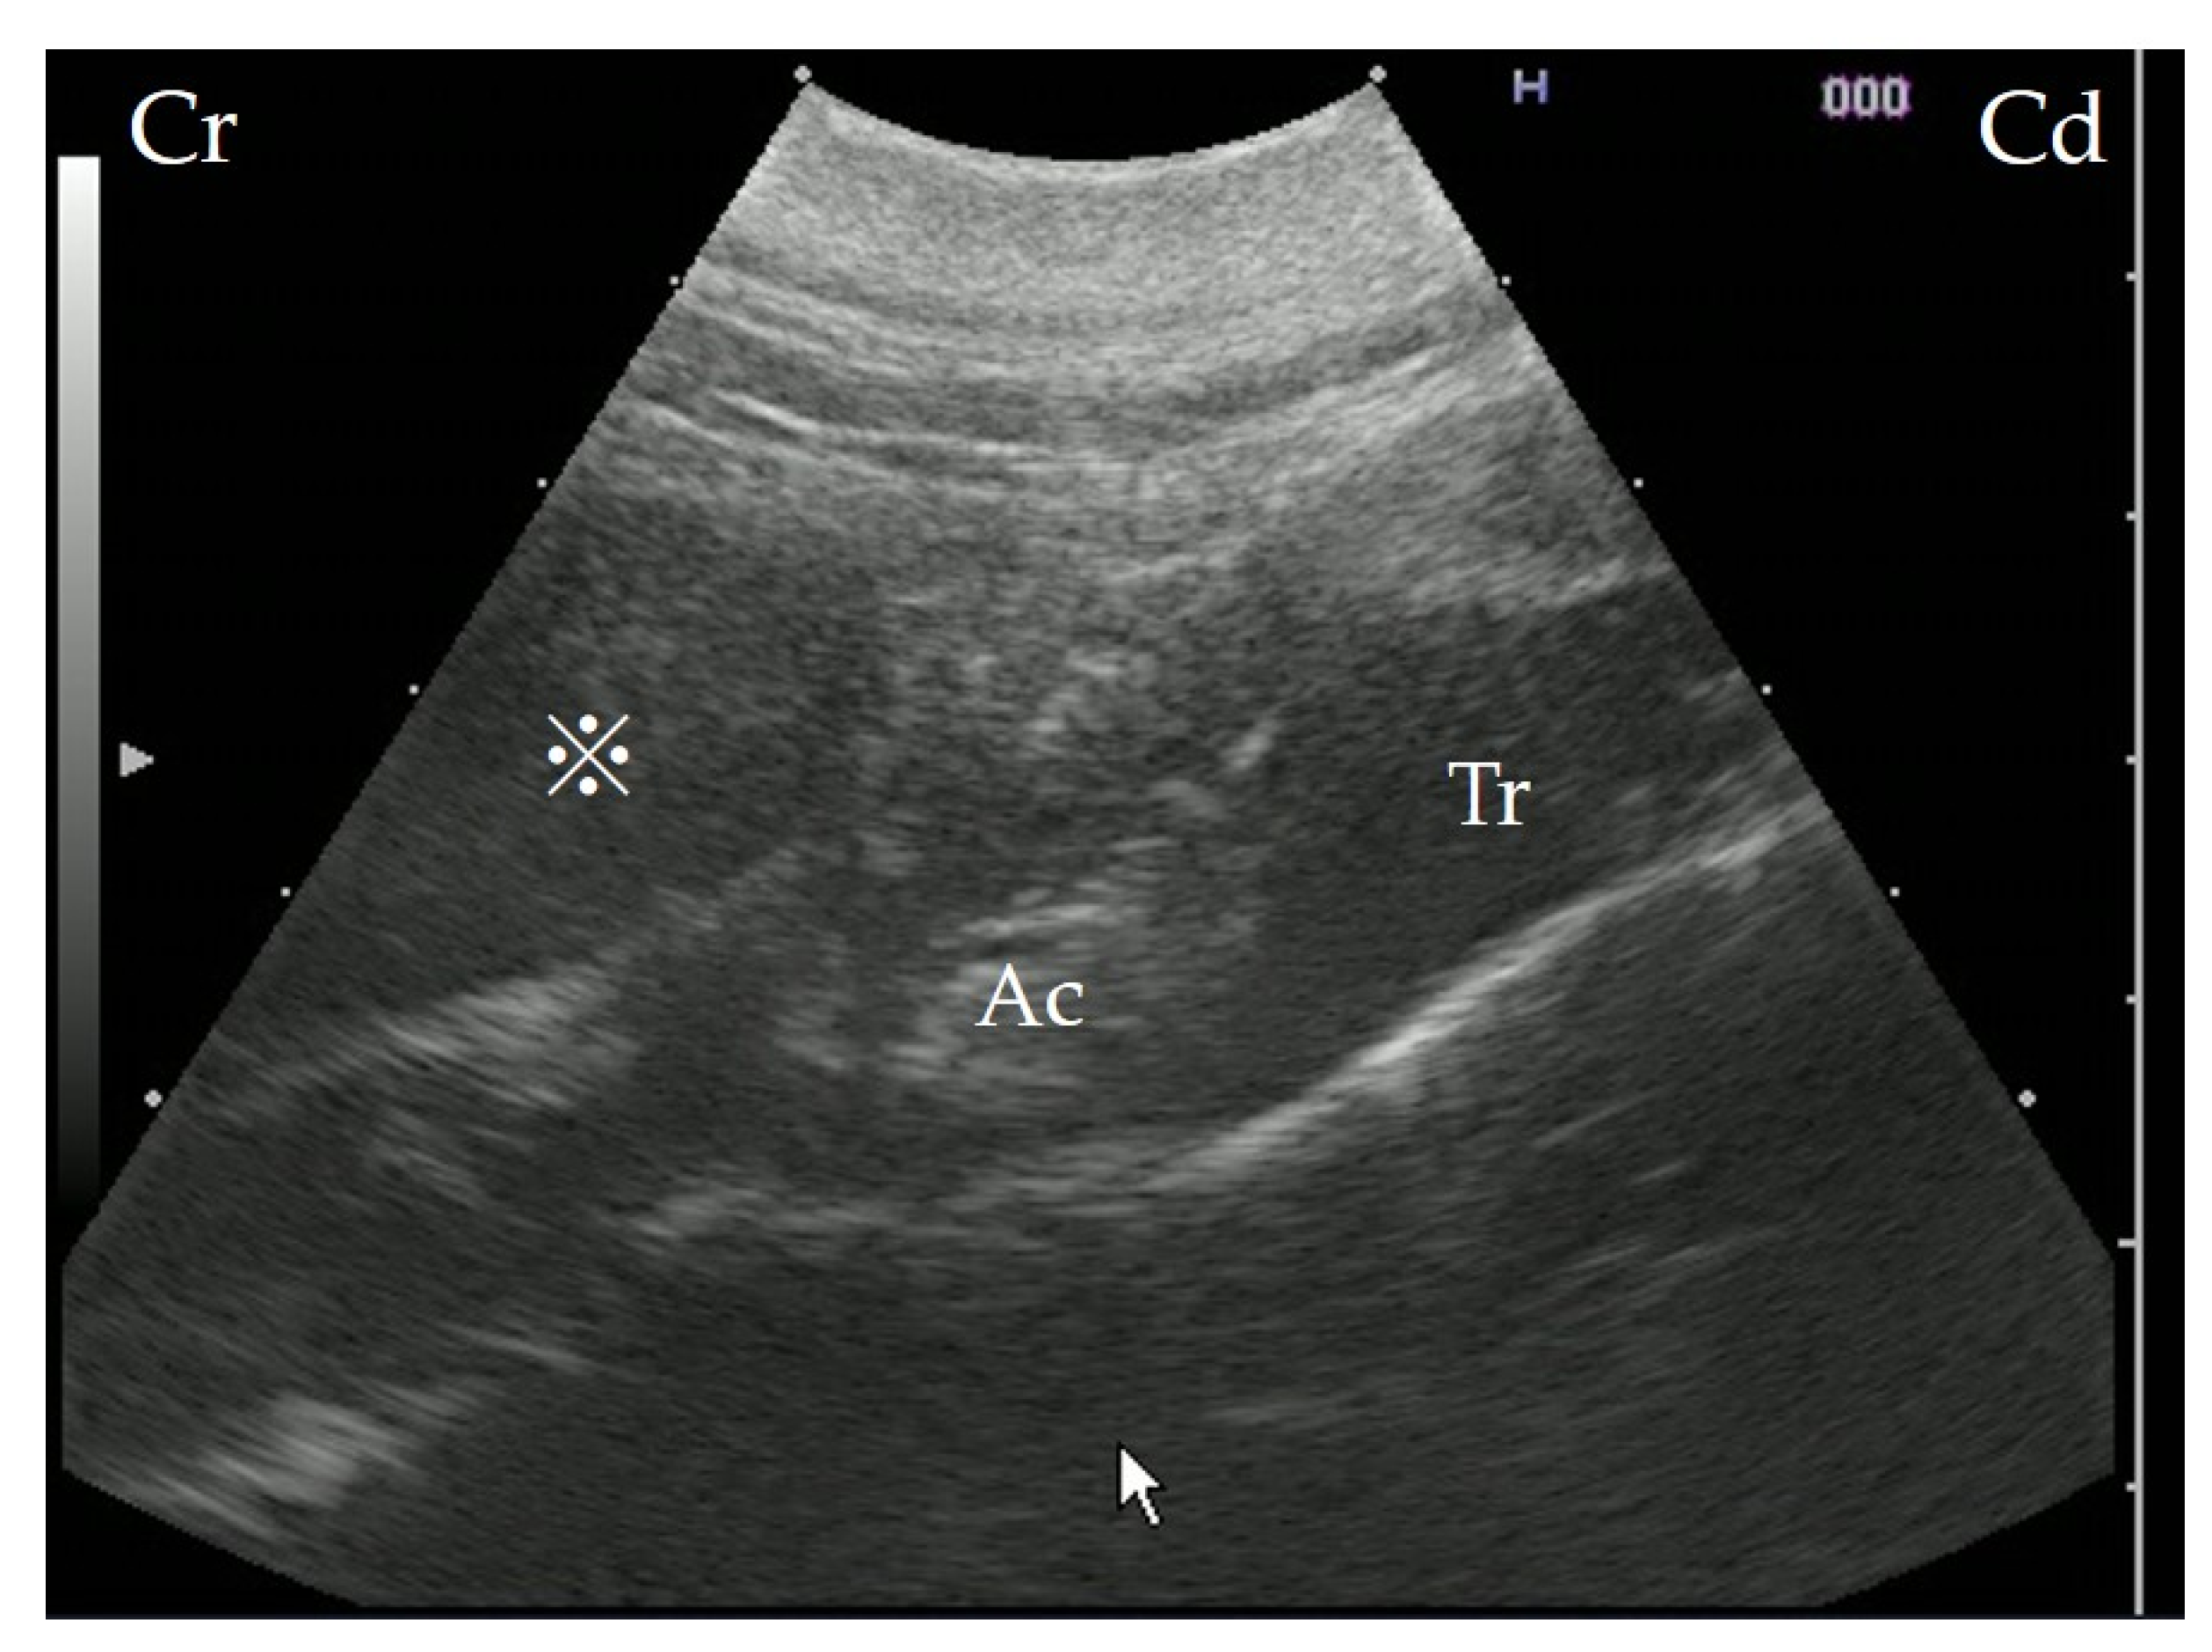

3.2. Radiographic Examination

In the orthostatic position, without sedation, horizontal radiography of the head was performed with a mobile X-ray unit (Sirius Star Mobile, FUJIFILM Healthcare, Tokyo, Japan) centered on the pharynx; it showed a mass with increased soft tissue density in the dorsolateral part of the pharynx. The mass was oval, measuring approximately 12 × 11 cm, with an internal line demarcating the lower radio-opaque region from the upper radiolucent region, indicating the presence of fluids (Figure 1).

Figure 1. Lateral radiography of the pharyngeal area of the cow showing a retropharyngeal abscess obstructing the laryngeal airway (arrowhead). The dashed line indicates the mass outline, and the arrow points to the horizontal demarcating line, which indicates the presence of fluids.